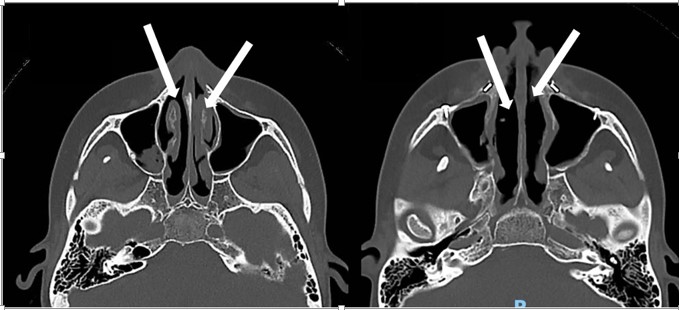

Inferior Turbinate Reduction

Maxillary intrusion or posterior repositioning may reduce intranasal space, causing inferior turbinate impingement [3, 7]. After down-fracture, the inferior turbinates are directly visible; partial turbinectomy is performed using electrocautery to reduce turbinate bulk and minimize postoperative airway obstruction (Figure 1).

This approach is particularly indicated in patients with turbinate hypertrophy or obstructive sleep apnea [7, 8].